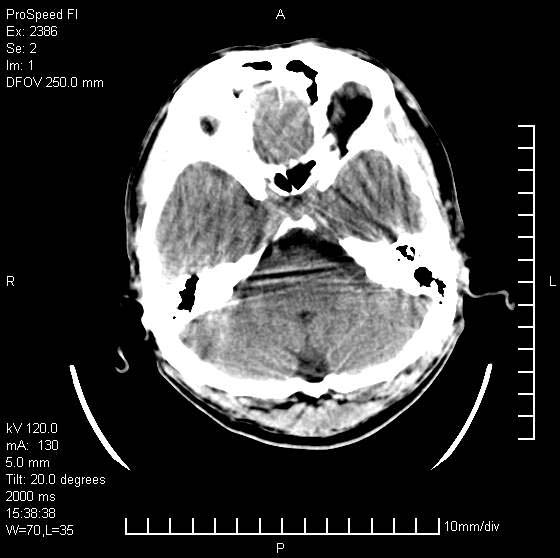

以下是引用天南地北在2007-9-19 18:43:00的发言:[br]典型慢性硬膜外血肿[br][br][本贴已被 天南地北 于 2007-9-19 18:44:11 修改过]

以下是引用曼一拍在2007-9-20 11:06:00的发言:[br]支持慢性硬膜下血肿.[br]慢性硬膜下积液:血肿有包膜,ct值稍高于脑脊液,增强可有染色。不典型者血肿可多呈梭形.是硬脑膜与蛛网膜之间的潜在腔隙内的血肿。[br]鉴别:[br]1\\硬膜外血肿:是颅脑外伤后脑膜或板障内血管破裂,血液在颅骨与硬膜之间积聚所致.通常是脑膜动脉破裂,也可因静脉窦破裂或颅骨的板障静脉出血,发生于外伤的着力部,常与颅骨骨折并存。脑膜动脉出血则急,若是板障静脉出血在则可有慢性。[br]2\\硬膜下积液:(硬膜下水瘤)[br]是由于蛛网膜破裂,脑脊液经蛛网膜破口进入硬膜下腔不能回流。或水肿阻塞而形成。[br]ct表现:颅骨内板下方新月形低密度区近似脑脊液密度;占位效应清,周围无脑水肿。[br]